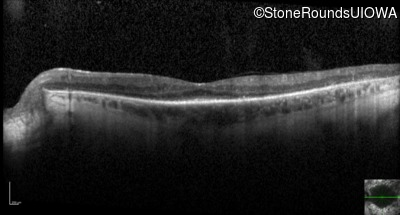

Optical Coherence Tomography - Right - 20/25 +1

Exemplar / OCT Stack

OCT Stack